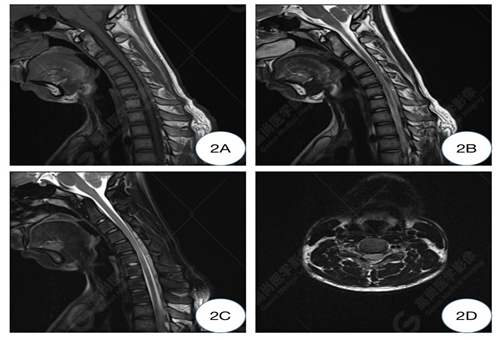

2A-2C圖、曲頸位T1WI及T2WI矢狀位圖示C5-6水平頸髓變細(xì)明顯,后方硬脊膜向前移位,并壓迫頸髓,硬膜外間隙增寬并其內(nèi)見(jiàn)條索狀低信號(hào)影;2D圖、曲頸位T2WI橫軸位圖示C5-6水平椎管變窄,相應(yīng)水平頸髓形態(tài)變扁平,呈受壓改變。

C5-6椎體水平頸髓及曲頸位頸椎異常改變,可符合平山病表現(xiàn)。

影像學(xué)常規(guī)中立位可表現(xiàn)為下頸椎和頸背交界處的脊髓萎縮變平,神經(jīng)膠質(zhì)增生區(qū)域在T2WI序列顯示為高信號(hào),有時(shí)僅表現(xiàn)出可疑征象,需補(bǔ)充屈曲位掃描。HD 在屈曲 MRI 上具有特征性的成像特征。屈曲位MRI顯示,低位的頸髓向前移位,受壓變扁平,可合并萎縮,后部的硬腦膜向前移位,后硬膜外間隙增寬,形成新月形區(qū)域,并有異常信號(hào)改變及流空血管影,增強(qiáng)掃描硬膜外異常信號(hào)常呈明顯強(qiáng)化,提示其為充血的后靜脈叢可能,因?yàn)槠湓谥辛⑽粧呙钑r(shí)完全消失。